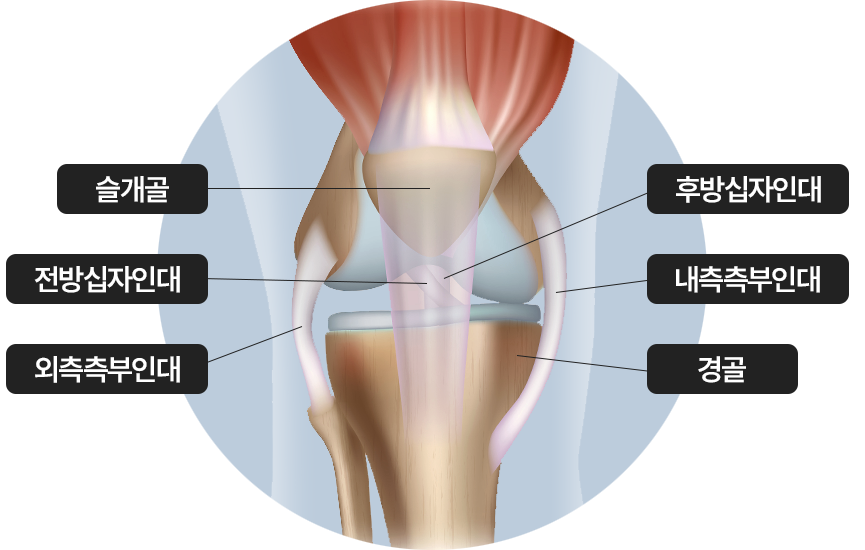

무릎관절의 큰 충격, 과도한 회전, 갑작스러운 움직임으로 인해 전후방 십자인대나

측부 인대 손상

무릎관절의 인대, 힘줄, 연골, 반월상 연골판, 뼈 등